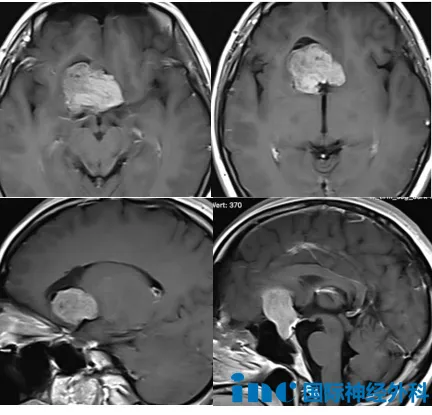

她被诊断为鞍区巨大占位,肿瘤已达32×33×43mm,双侧大脑前动脉明显受压移位。医生建议开颅手术,但也坦言风险很高。此时,她右侧视野已出现明显缺损,记忆力和体力悄然下降,还发生了癫痫。面对如此复杂的病情,武女士一家在焦虑中寻找希望——怎样才能得到国际大咖的治疗?

这台手术的关键在于鞍内部分——这里是肿瘤的起源位置,也是垂体和垂体柄所在的重要区域。巴特朗菲教授在术前分析中指出:“这部分必须极为谨慎地处理,以保护垂体功能不受影响。同时,肿瘤已累及大脑前动脉,血管保护至关重要。”

今天,在巴教授的主刀下,在国内神经外科团队的配合中,肿瘤切除满意,保留垂体柄结构。